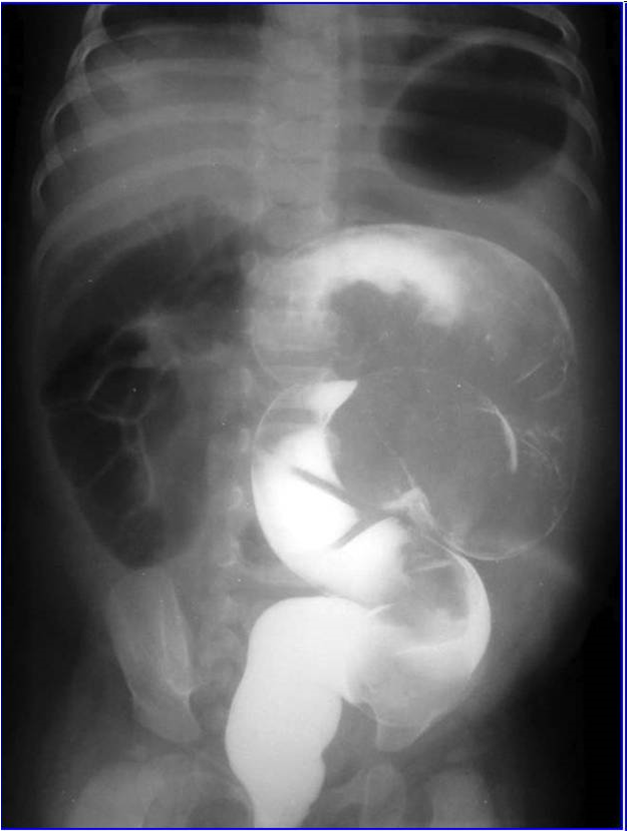

Usus berbentuk seperti tabung yang panjang. Intususepsi adalah gangguan di mana salah satu bagian dari usus (biasanya usus kecil) terselip ke bagian lain. Peristiwa ini kadang-kadang disebut sebagai "telescoping" karena mirip dengan cara lipatan teleskop ketika dilipat bersama-sama.

Sebuah terapi yang disebut barium atau enema udara biasanya dapat memperbaiki dan berhasil mengobati intususepsi. Jika enema bekerja, perawatan lebih lanjut tidak diperlukan.